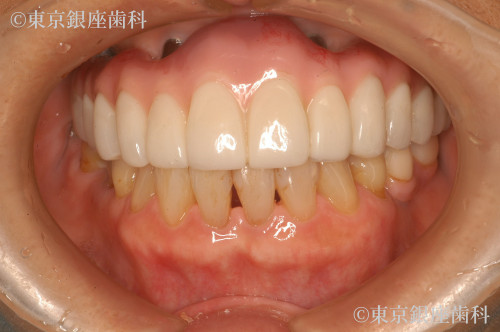

Before

After